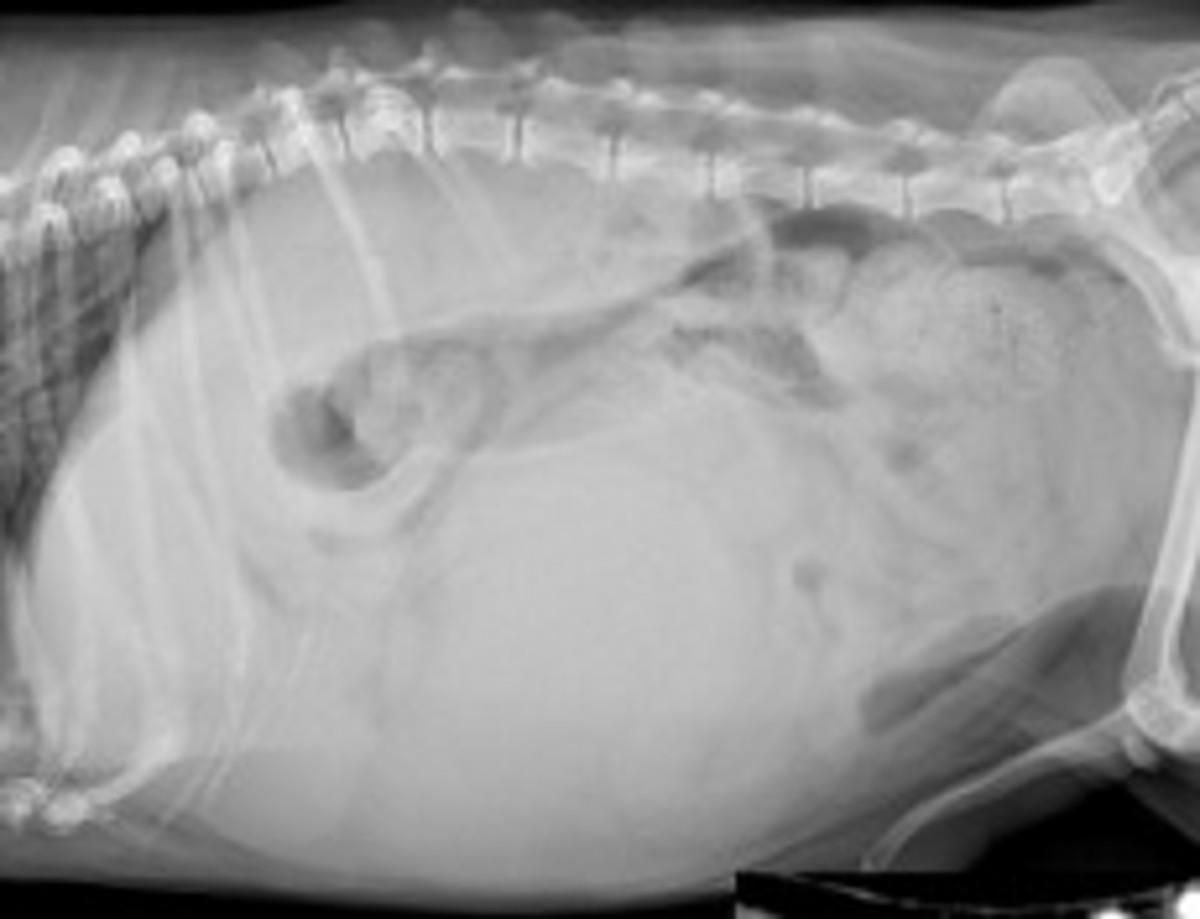

ヨークシャーテリア、未去勢雄、12歳、体重3.4 kg(BCS3/5)です(図8)。両眼の羞明を主訴に近医を受診し、その時の検査にて肝臓に腫瘤が見つかったため、肝臓腫瘤に対する精査および治療を求めて紹介受診しました。初診時の血液検査では、低血糖およびGPTの上昇が認められました(表3)。X線検査および超音波検査にて肝右葉に腫瘤が認められたため(図9)、CT検査を実施しました。CT検査では肝右葉から突出し、周囲肝組織と比較して低吸収を示す腫瘤(6.0×6.0×7.9 cm)が孤立性に認められました(図10)。これら検査所見や造影剤による染色性から肝右葉に主座する孤立性の肝細胞癌が疑われました。また、肝腫瘍以外に低血糖の原因となる異常が認められなかったため、低血糖は腫瘍随伴症候群であることが疑われました。肝腫瘤は外科的に完全切除が可能と考えられたため、開腹下で切除する計画としました。周術期の血糖管理については、先の門脈体循環シャントの症例とほぼ同様に計画しましたが、本症例では腫瘍切除後、腫瘍からのインスリン様成長因子の分泌がなくなることから、高血糖になることが想定されましたので、腫瘍切除後は血糖値をモニターしながらグルコースの輸液を減じることを予定しました。

図9 単純X線検査 ラテラル像